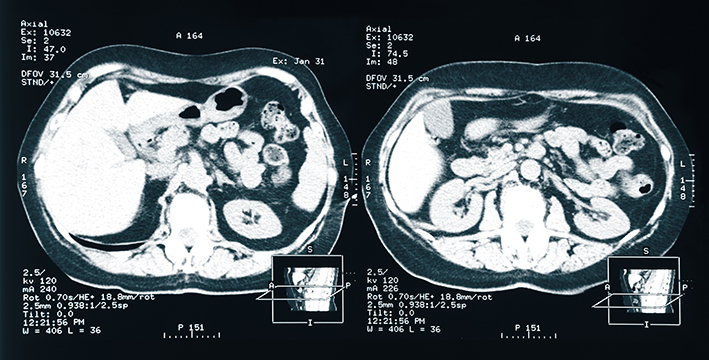

Die akute Nierenschädigung ist eine häufige Komplikation bei Patient:innen auf Intensivstationen und ist mit einem hohen Risiko für Tod, Folgekomplikationen und Ressourcenverbrauch verbunden. Viele dieser Patient:innen erhalten eine Nierenersatztherapie. Diese wird zur Behandlung schwerwiegender Stoffwechselstörungen (z.B. Azidose, Hyperkaliämie, Urämie) und Störungen im Flüssigkeitshaushalt benötigt (Überwässerung). Nach wie vor ist es jedoch unklar, wann genau mit einer Nierenersatztherapie begonnen werden soll.

Bislang gab es um den Zeitpunkt einer Nierenersatztherapie widersprüchliche Meinungen. „Es gibt Kolleg:innen, die für frühe Maßnahmen eintreten, anderer für spätere“, kennt Michael Joannidis, Direktor der Gemeinsamen Einrichtung für Internistische Notfall- und Intensivmedizin, die Problematik wobei die Tendenz hin zu früheren Maßnahmen geht: „Bisher war die gängige Meinung, dass man bei einer akuten Nierenschädigung bei Intensivpatient:innen relativ früh mit der Nierenersatztherapie beginnen soll, um das Akkumulieren von Giftstoffen zu vermeiden.“ Grundsätzlich ist die Nierenersatztherapie ein Verfahren, das sehr gut toleriert wird und selten Nebenwirkungen hat. Joannids gibt allerdings zu bedenken: „Eine Nierenersatztherapie ist ein Eingriff: Man benötigt einen großlumigen Katheter, das Blut kommt in einen externen Kreislauf und kommt somit mit Kunststoffoberflächen in Berührung, was einen gewissen Entzündungsreiz darstellt. Weiters wird das Blut zur Entfernung von Giftstoffen gefiltert, allerdings gehen bei diesem Prozess unter Umständen auch nützliche Stoffe verloren“, sagt Joannidis.